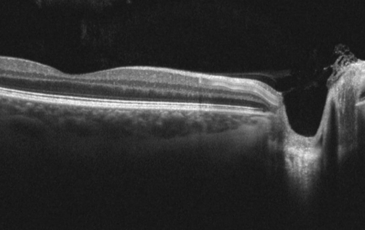

Our eye examinations aren’t just a basic test of your sight. Your optometrist will test you for conditions like glaucoma, age-related macular degeneration (AMD) and cataracts. We recommend an enhanced eye examination for all, which includes even more time with the optometrist and scanning with the state of the art 3D optical coherence tomographer (OCT) machine. We were proud to be the first practice in the area to be able to provide this service in 2010, and the data we have from seeing patients regularly since has been invaluable in helping us detect conditions in their early stages.

This is an in-depth examination of all aspects of your vision and eye health and includes examination with the state of the art 3D OCT scanning machine. You can chose to include this in your Eyeplan scheme for just £2 a month.